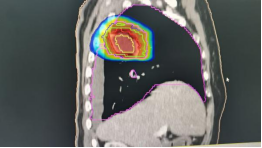

2、咽部肿瘤横断面及矢状面治疗剂量显示图

3、计划系统效果图:黄色线内-蓝色线外深颜色区域为高剂量区域,黄色线外及蓝色线内为低剂量区域。即照射剂量区域可按肿瘤治疗的需要进行调节。